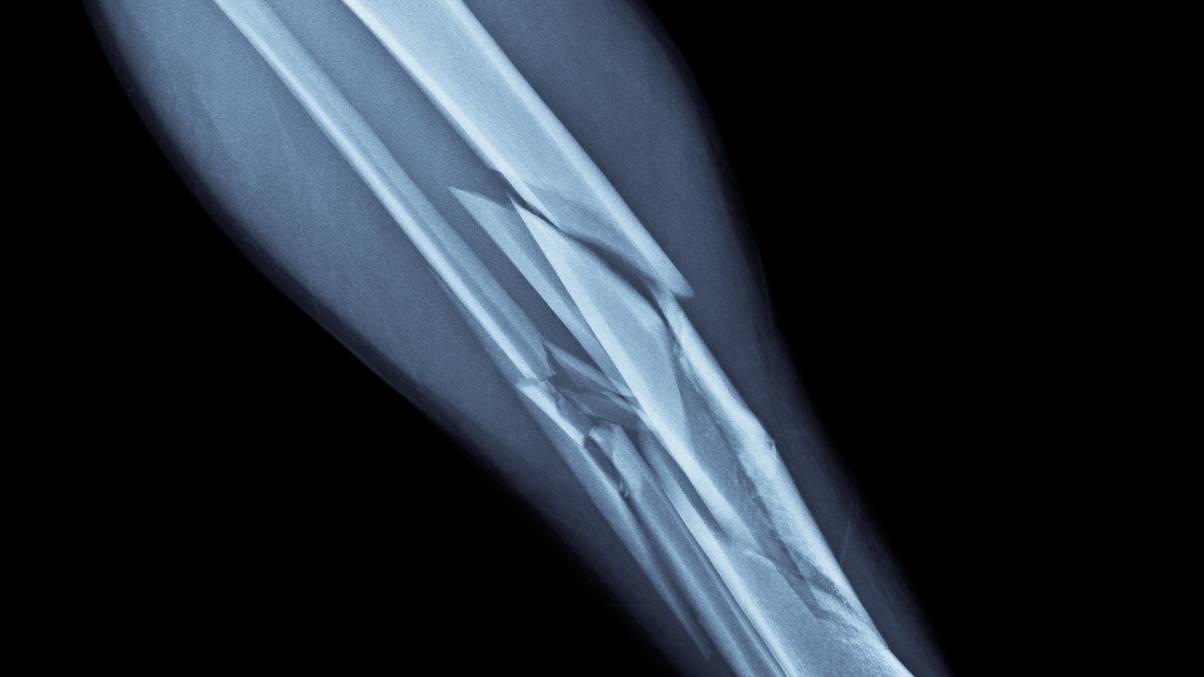

Damaged bones are an unlucky a part of life and their is not an age restrict on them, however some fortunate buggers handle to dodge them utterly. They’re typically the results of clumsy accidents and traumatic falls, whereas folks with underlying well being situations could be very inclined to them too.

It seems that the bones of a grown up are much more fragile than these of a small baby, as adolescents boast a ‘distinctive high quality that enable their bones to heal quicker’.

In response to consultants at Complete Orthopaedic Care, a US agency who present complete orthopaedic and bodily remedy providers, grownup bones can take months to fix themselves whereas children could be again on their ft in only a matter of weeks.

“Not like the bones within the grownup physique, the bones of kids are nonetheless rising, so their development sample can extra simply accommodate damaged or fractured bones,” it explains.

Anyway, the consultants clarify that youngsters have this superpower as a result of the ‘bones of a kid include much more periosteum, [which is] a dense layer of vascular connective tissue overlaying their bones’.

Complete Orthopaedic Care notes: “Not solely does this make their bones thicker and stronger, but it surely additionally means restoration and therapeutic time is far faster.